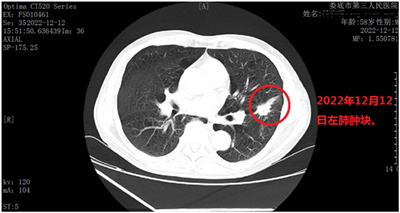

202212月,新冠疫情肆虐,全国人民诚惶诚恐,谈新冠色变,很多人稍有咳嗽就来医院做肺部CT,生怕感染新冠变白肺。患者杨某某,就是这些人中的一个,由于咳嗽来娄底市第三人民医院查肺部CT,没有发现白肺,却发现左肺下叶内前底段叶间裂旁见大小约29X14mm结节状高密度灶,其内可见空泡影,边缘毛糙,可见不规则毛刺、分叶及棘状突起,叶间胸膜牵位轻度移位,LU-RADS4C类,考虑周围型肺癌(见下图)。

1212日患者在娄底市第三人民医院肿瘤科行肺穿刺活检,确诊为左肺低分化腺癌(见下图),建议手术切除,患者由于个人原因拒绝手术治疗,要求保守治疗。